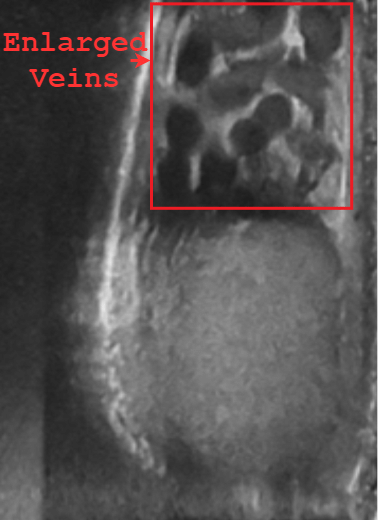

https://adsense.google.com/adsense/u/1/pub-9161951367286286/myads/sites/preview?url=notion6988.tistory.com 💡 정계정맥류, 자연 치유는 어렵지만 비수술 치료는 가능